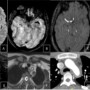

A. DWI axial shows restricted diffusion in left posterior putamen, suggestive of acute infarct

B.SWI axial shows long segment blooming (susceptibility vessel sign) involving left M1 segment of the MCA.

C. TOF MRA brain shows corresponding loss of flow signal along the left MCA

D. TOF MRA neck shows non visualization of the left subclavian, common carotid, internal and external carotid and left vertebral arteries

E. Axial source images of TOF MRA Neck shows thickening of the distal aortic arch

F. Axial T2 images of thorax show loss of flow void and wall thickening in left common carotid and subclavian arteries

G. AXial CTA re-demonstrates wall thickening along the distal aortic arch. H. Sagittal MIP of CT Angiogram also shows thickening along mid and distal thoracic aorta

A FLAIR Axial shows chronic infarct in the left posterior putamen

B SWI axial shows peripheral hemosiderin staining s/o hemorrhagic gliosis

C TOF MRA shows interval recanalization of left MCA

C CT angiogram shows interval decrease in the wall thickening involving distal arch of aorta.